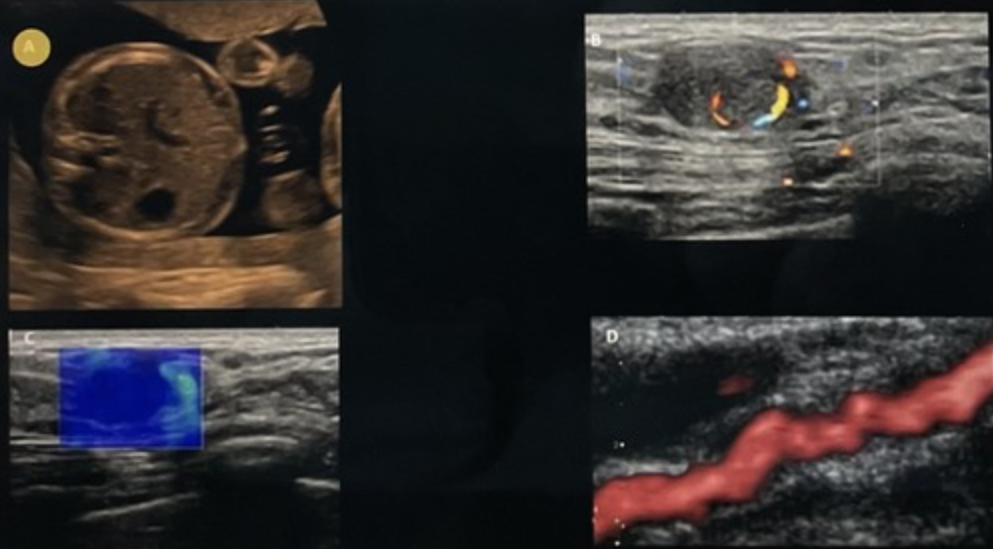

<p>Which of the following imaging techniques is designed to improve contrast resolution?</p><p>a. top left<br>b. top right <br>c. bottom left <br>d.bottom right</p>

Which of the following imaging techniques is designed to improve contrast resolution?

a. top left

b. top right

c. bottom left

d.bottom right

top left